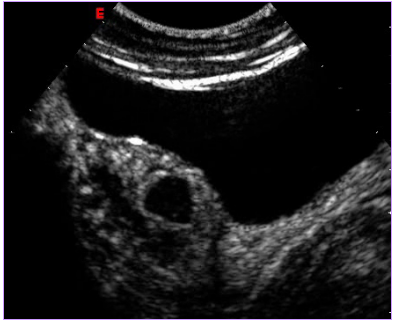

治療后壞死的子宮肌瘤不會消失,而是會發生纖維化,緩慢縮小,但對人體已經沒有危害了。最近,由于磁共振增強掃描(圖1,2)和超聲造影檢查技術(圖3,4)的應用,使治療效果的評價更加客觀和明確。

圖4 治療后6個月超聲造影